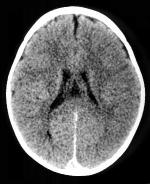

CT-scan van het hoofd

Een CT-scan van de hersenen kan uitgevoerd worden met of zonder contrasttoediening. Welke methode gebruikt wordt is afhankelijk van de indicatie. In sommige gevallen kan het aangewezen zijn het onderzoek eerst zonder en daarna met contrast uit te voeren om een duidelijker beeld te verkrijgen in de pathologie van de patiënt.

Bij een trauma kan de radioloog de genomen beelden ook interpreteren in een venster waarin de beenderstructuren duidelijker zichtbaar zijn.

Indien er contrast toegediend zal worden, is het noodzakelijk om nuchter te zijn voor het onderzoek. Best is hiervoor om minstens vier uur voor het onderzoek niet te eten of te drinken.